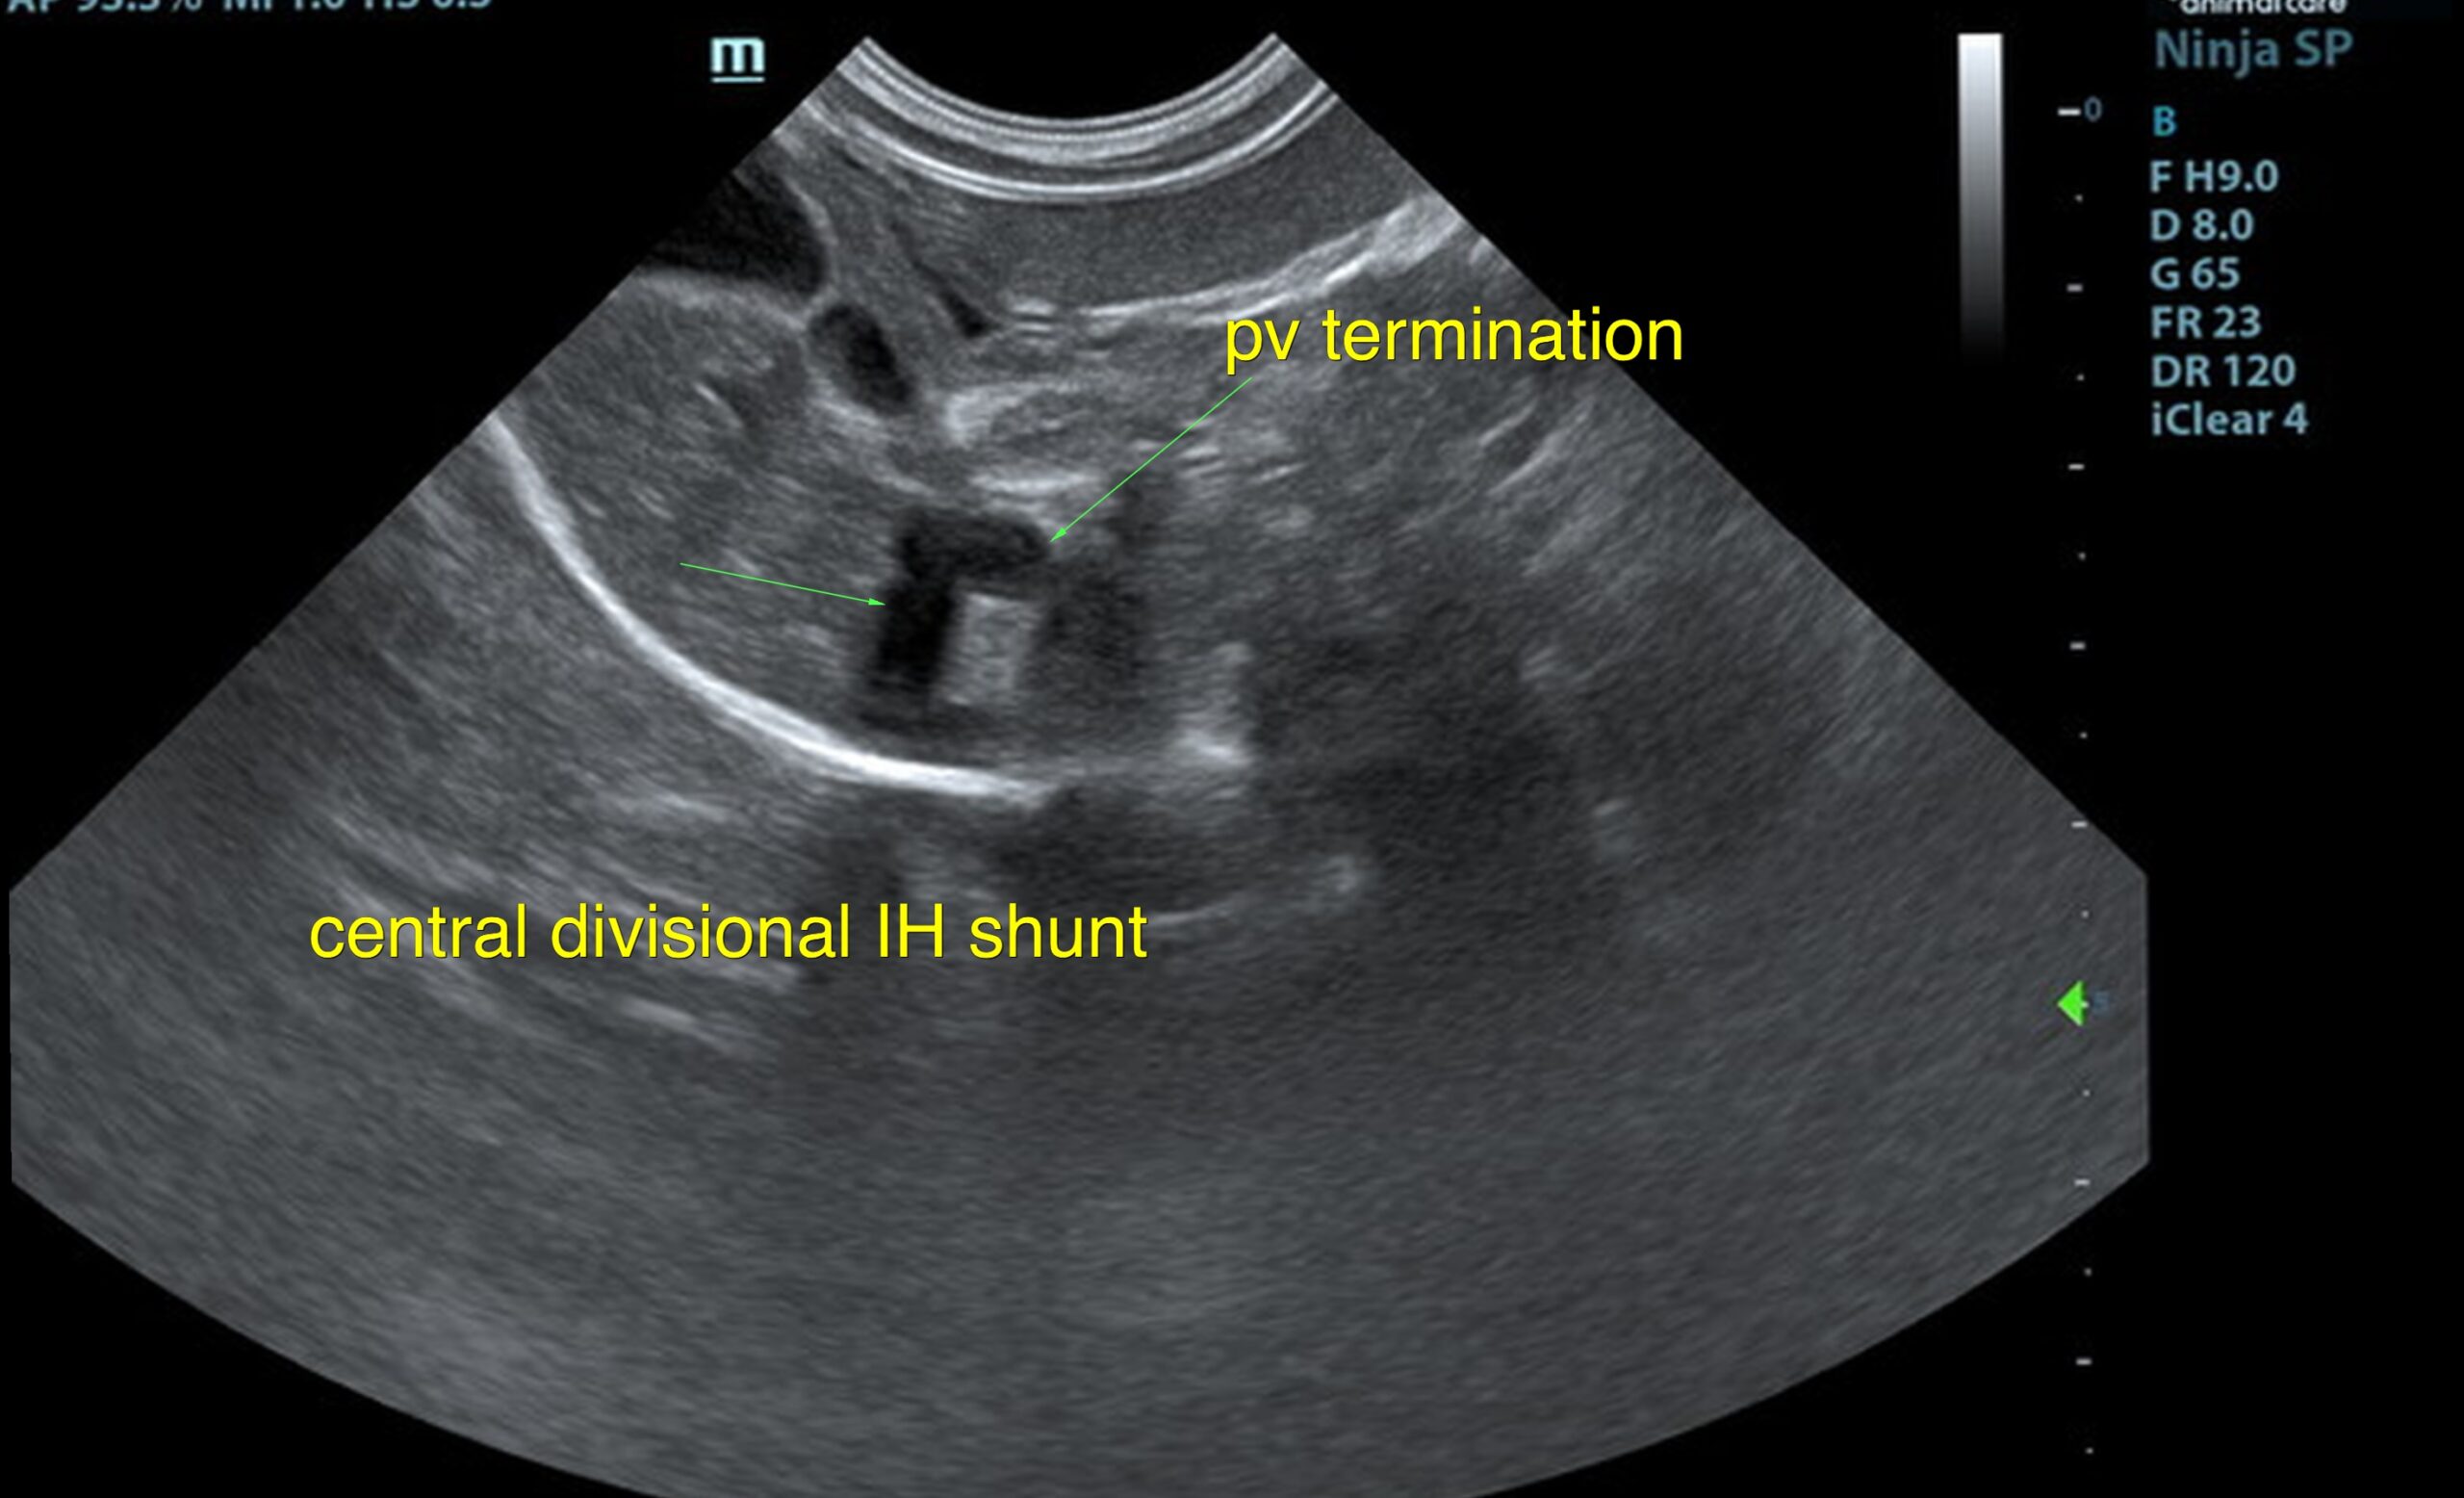

The liver was subnormal in size, yet the portal vein and vena cava ratio was 1:1. The portal veins were subnormal in size and measured 0.34 cm. The vena cava was enlarged and measured 0.34 cm. The vena cava was enlarged and measured 0.72 cm, aorta measured 0.4 cm. The branching of the portal vein appeared to be normal and of adequate volume. The portal vein and vena cava measured 0.5 cm each in the extrahepatic space. The splenic vein entry into the portal vein and gastroduodenal vein entry into the portal vein appear to be normal. There was one turbulent vessel in the region of the central branch of the portal vein, which may represent an intrahepatic shunt, but this could not be confirmed. The width of the shunt is approximately 0.76 cm. This is in position of central divisional shunt; however, right divisional origin cannot be completely ruled out. The gallbladder presented acceptably thin walls with primarily anechoic content. The cystic and common bile ducts were normal.